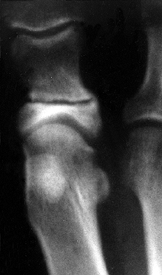

Measure the distal metatarsal articular

angle (DMAA), which is the relationship of the articular surface to the

long axis of the metatarsal. Normally, this should be less than 10° of

lateral deviation (Fig. 112.3).

Figure 112.3.

Radiograph demonstrating the distal metatarsal articular angle, which

measures the relationship between the articular surface of the

metatarsal and the long axis of the first metatarsal. Normal should be

less than 10° of lateral deviation.